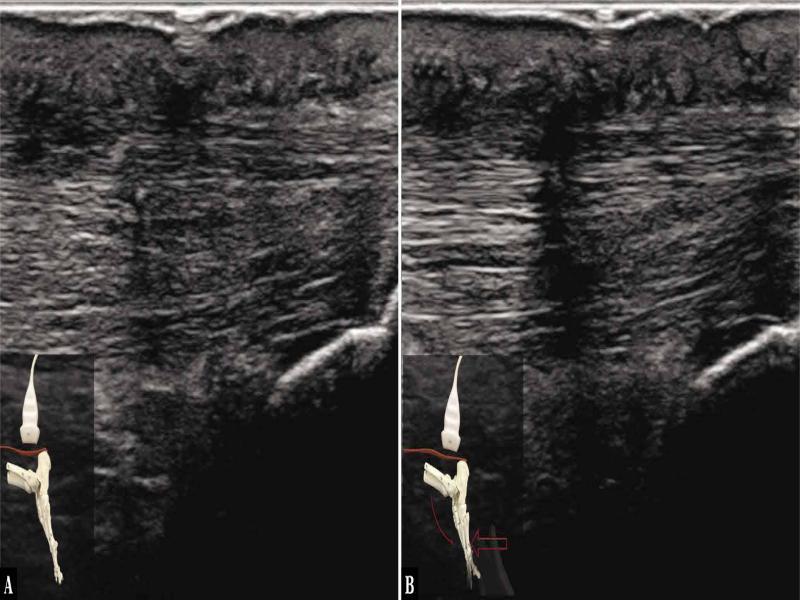

Fig. 2.

![Ultrasound examination protocol. A. The transducer is applied along the AT, above the calcaneal tuberosity. The tendon tension is present at rest. B. An 18–5 MHz US image of a tendon at post-rupture remodelling phase (4.5 months postoperatively). A longitudinal plane, a linear arrangement of AT fibres [red short lines]; the image indicates the presence of resting tension. [red arrows mark the borders of the tendon]](https://sciendo-parsed.s3.eu-central-1.amazonaws.com/64722e23215d2f6c89dbec00/j_jou.2021.0043_fig_002.jpg?X-Amz-Algorithm=AWS4-HMAC-SHA256&X-Amz-Content-Sha256=UNSIGNED-PAYLOAD&X-Amz-Credential=ASIA6AP2G7AKBY2AOJTK%2F20251216%2Feu-central-1%2Fs3%2Faws4_request&X-Amz-Date=20251216T170210Z&X-Amz-Expires=3600&X-Amz-Security-Token=IQoJb3JpZ2luX2VjEJ%2F%2F%2F%2F%2F%2F%2F%2F%2F%2F%2FwEaDGV1LWNlbnRyYWwtMSJIMEYCIQDpGWJy5nYmL6vQIHHt%2BcL%2F3OSMUmRuP2Jq%2F0ZR1%2FLQBwIhAMOCdMyV4r3yYa%2BF%2FudRVaQIR4fmJylEiwzwqN7lTdT5KrwFCGgQAhoMOTYzMTM0Mjg5OTQwIgz4VpTpHrGQ%2BRwhfVIqmQUmdJgnr7B%2F2TCxvDKqjEoGFRsgxmY1WO7B2uHZlmD80cdU17oWnLhWozEmhOcl3%2FA2q7bDkKBAuPcFO1a7dNHauScY2SzHlX0kIwGWBTyagWuMSXxWSKl7tuRn79BzKKKgACwrvnuaElPejVfsbXCLbokYmV3F5d6L7ZvYrBqtQi69XC21CoAlb8Y6i6%2FgGjbHb96ZBwCqvP7cOXSUTpBBNcWXDb3SBoKgMOvVGHUg3rSkHFBWbeUJWEqFQuQLNZGIPzAiqdGcNpaQoxwYfz5gf2hRAObi1TmBBQCJk0SxpwaFBWoacduWkTQZ5HNbLbV2Y7aFE3mDRSzYCiCfLMQh7Mgepw0nBxMmfE85hi32y%2BHl0YbHclUDfuc6cLW%2FYcTSrFNW5DY1zlMhrYkTdcHwhlV1hhIJTQNjAopybRxyhl8UYT%2FarnBEwsCeDtNSkjr%2BbyoA4Mb304CzPuGRdqK9emQVbV5UYjlPpV4HDHxB%2Feh%2FvM4JIZO4n8g6cp3NqtH4DmY0IW9MSRtklWQp1NGIx%2FvKjGOq7aOzqrJapYKvKLlD5e4RXY6v%2FiOPFbAdlTfn5%2FqC4BWLoxMGssJ9k0H38JHeskVYSwPhVqIo0EtaUeEaKSM06dRorQWA4zp9F2C8ovAo54ubZDzgUdOR0AQTvRjPzuFLiqLDfhn7QV8H0gLPqSM190VJgPIW5IZZPui4U7%2FBneLPSyQBM0j6QtUb8Mst%2FeYnWZLJMIdEPA%2Bv6au%2BzISiEhwEeyP69vVeq%2B5DRurxZDk6yvkPWt7OPS0VcMYYkMEE%2FBKpoOMCHV5smh95YG7YQar4J%2FuRfCRSBakAngbpy9rbUzTx0nincY30w2DOtdkRQ%2B6llm11f5dKO2lDvaYDR9zwsjDY3YXKBjqwAWriJvfX%2BElci0gwZQievDMAbkmHC4QI%2FqxewR1beknZpaCkRtCONkVDPkjy%2BT4qSFomaXZUpQZ4%2FUCmLMIxbgvXVx2C%2F8RvVqLErXggh0KomRU%2B0YjqHSFLW6f4wXhBudqG47DjGNdcJofTT2PytMHHltz%2Fhgs2cVWnTfkhMiVrxvUgXovn9cYHmefQfFeOjU7b7EZJzwNBhn624LDbKUNBrlDn2%2FKsMwkUHsc1t%2Flz&X-Amz-Signature=6a075bdf77cc39f77ac1b62bb2f79d1d0ccd30fbb6a3ab3b41663d1783cafa39&X-Amz-SignedHeaders=host&x-amz-checksum-mode=ENABLED&x-id=GetObject)